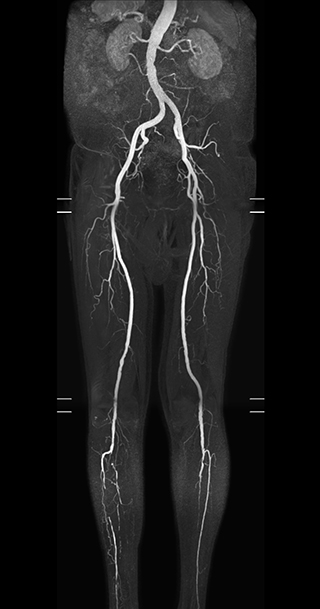

MRA run-off study with mDIXON

The subtractionless peripheral MR angiography shows improved vessel-to-background contrast and high resolution. Ingenia Ambition 1.5T.

Station

Ingenia Ambition

Pelvis

Voxels 1.3 x 1.3 x 3.2 mm, FOV 430 mm, 125 slices

Upper legs

Lower legs

Voxels 1.0 x 0.82 x 2.0 mm, FOV 430 mm, 125 slices